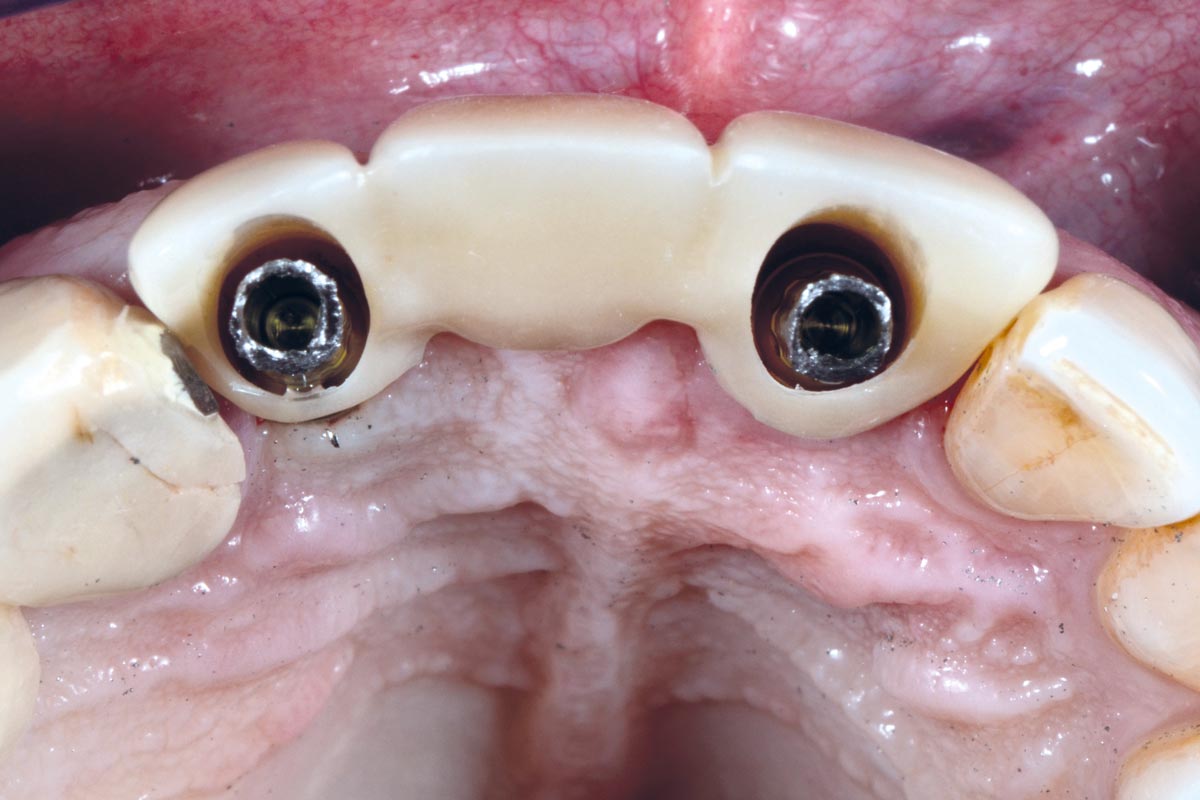

15/17 - Implant placement 6 months post-operative. Prosthetic restoration.

Socket preservation using cerabone® and Straumann® Emdogain® - Dr. S. Pelekanos